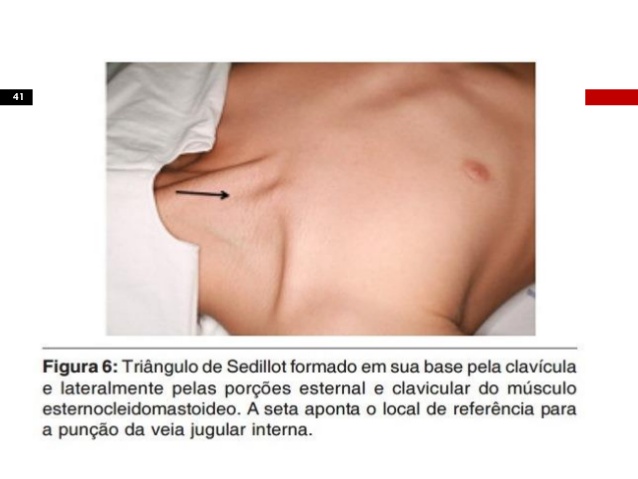

A veia jugular interna situa-se ântero-lateralmente à artéria carótida interna, na sua metade proximal sob o músculo esternocleidomastóideo e sua metade distal no triângulo formado pelas porções clavicular e esternal do músculo esternocleidomastóideo, e pela clavícula. Une-se com a veia subclávia sob o terço proximal da clavícula.

A VJI tem trajeto relativamente constante, porém pode sofrer variações anatômicas. deve ser dado preferência a punção da jugular direita pelo menor risco de lesão da cúpula pleural e impossibilidade de lesão do ducto torácico.

- Localizar o local de punção: VJI – ápice do triângulo das inserções do ESCM; VSC – Ponto Médio do terço médio da clavícula;